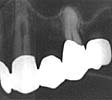

Bild 1 |

Bild 2 |

49-årig kvinnlig patient,

kirurgisk endodonti 23, traditionell teknik. Perforation juxtaraadikulärt (bild 1).

Marginal kommunikation till destrukuktionen förelåg vilket konstaterades preoperativt. |

Ett år efter ingreppet föreligger

avslutad läkning, ingen kvarstående ficka (bild 2). Luxalloy användes som retrogradt

fyllningsmaterial.